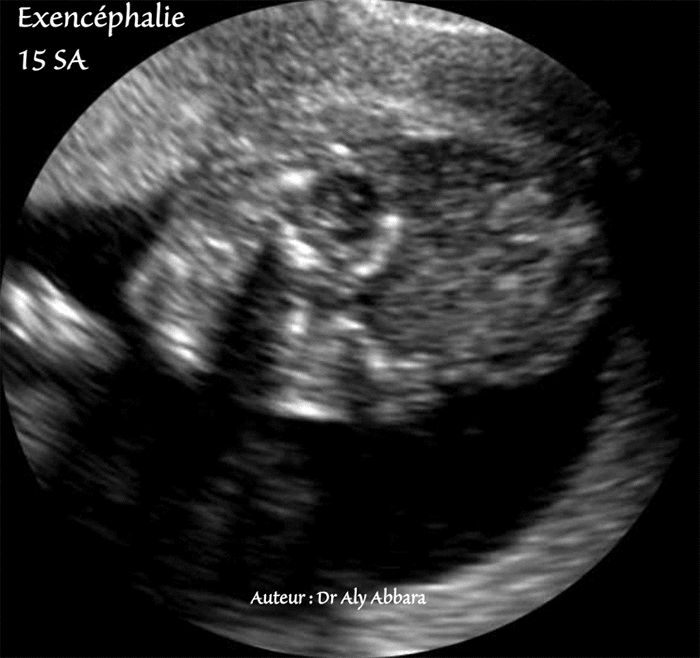

Exencéphalie - 15 SA - Coupe échographique frontale (coronale)

Image échographique montrant les anomalies anatomiques caractérisant l'exencéphalie

(Pôle céphalique vu de face)

Chez ce fœtus âgé de 15 SA, on constate la présence de la séquence polymalformaitve du

cordon court avec des adhérences amniotiques

En raison de l'aplasie de la voûte crânienne, on peut observer à l'échographie prénatale le cerveau (sur développé, dysplasique et désorganisé) et les méninges flottant dans le liquide amniotique. L'exencéphalie évolue vers l'anencéphalie car les traumatismes directs et l'agression permanente par le liquide amniotique du cerveau non recouvert par la voûte crânienne entraînent sa destruction totale secondaire vers la 8e - 10e semaines de gestation.